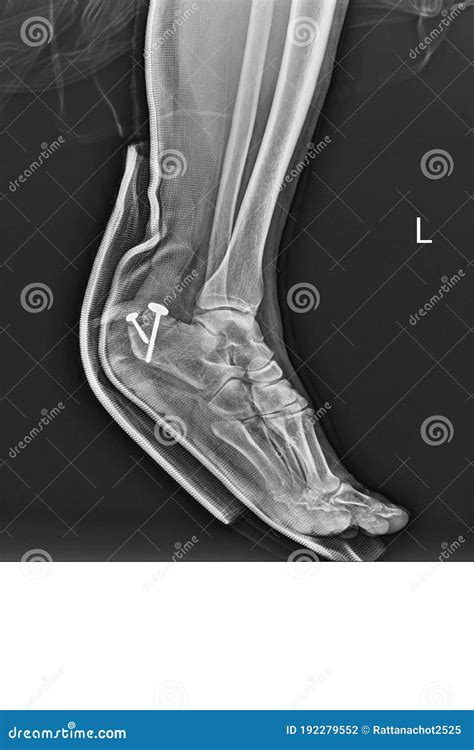

• Surgery: In cases of severe fractures or dislocations, surgery may be necessary to realign the bones and stabilize the joint. Surgical options may include open reduction and internal fixation (ORIF) or arthroscopy.

• Fractures: These can range from simple cracks to complex fractures involving multiple bone fragments. The location and severity of the fracture will determine the appropriate treatment.

• Dislocations: These occur when the bones in the heel area are displaced from their normal position. Dislocations can cause significant pain and may require surgical intervention.